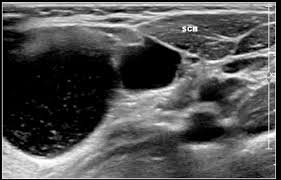

Air and bone also reflect sound waves. A lump in the neck —cancers that begin in the head or neck usually spread to lymph nodes in the neck before they spread elsewhere. A neck ultrasound may help diagnose (find): Breast ultrasound images are seen from superficial (skin) to deep (chest wall muscle) over a segment of tissue. A neck ultrasound can be used to observe the thyroid gland to look for nodules, growths, or tumors. But now i am worried that the reason the lump didn't show on the ultrasound is because it is actually under the skin in my neck (i.e in my throat) rather than on my actual thyroid/neck. David dang answered 14 years experience radiology node, cyst or others: A small lump on the neck usually is a lymph node, a small sebaceous cyst or a lipoma, although it could be something else. The most common symptom of thyroid cancer is a hard lump on the neck—but most patients experience no symptoms at all. This means that they are larger than about 1 centimeter (about 1/2 inch) across. Optimal positioning and exposure of the neck for ultrasound of the thyroid and parathyroid glands (a, b) and lateral neck for lymph node examination and mapping (c).while the vast majority of patients are supine on the exam table with a pillow supporting the shoulders to allow gentle neck extension, keep in mind that some patients have beautiful anatomy (d) that allows ultrasound exam even in. 1), and the presence of an echogenic hilus within lymph nodes was previously considered a sign of benignity. What does a healthy kidney look like on an ultrasound?

If your cancer diagnosis is based on an ultrasound, it could easily be wrong. But ultrasound is usually the first choice for looking at the thyroid and neck structures. Other causes for a neck mass may be due to cancers such as lymphoma, thyroid or salivary gland cancer, skin cancer, or cancer that has spread from somewhere else in the body. Cancerous lymph nodes can occur anywhere on the neck and are typically described as firm, painless, and sometimes may be immovable. As thyroid cancer gets more advanced, you might notice symptoms like: Cancerous neck masses in adults are most often due to head and neck squamous cell carcinoma (hnscc). An ultrasound of the neck is used to examine the carotid arteries located on each side of a patient's neck. Optimal positioning and exposure of the neck for ultrasound of the thyroid and parathyroid glands (a, b) and lateral neck for lymph node examination and mapping (c).while the vast majority of patients are supine on the exam table with a pillow supporting the shoulders to allow gentle neck extension, keep in mind that some patients have beautiful anatomy (d) that allows ultrasound exam even in. On ultrasound, a breast cancer tumor is often seen as hypoechoic, has irregular borders, and may appear spiculated. And my neck look like an old shapai. The breast tissue kind of looks like waves on the ocean. But now i am worried that the reason the lump didn't show on the ultrasound is because it is actually under the skin in my neck (i.e in my throat) rather than on my actual thyroid/neck. In the framework of such terms as ultrasound of the neck, can be performed the following studies:

If a biopsy is needed, doctors use ultrasound to scan the area again, ensuring that they know exactly where to place the needle. In addition, the following tests may be used to diagnose head and neck cancer: And my neck look like an old shapai. A lump will form when a cancer cell infiltrates the capsule and multiplies. These are frequently seen in nodules containing papillary thyroid cancer. But ultrasound is usually the first choice for looking at the thyroid and neck structures. The normal neck contains scores of lymph nodes some of which are easily seen with ultrasound. Ultrasound an ultrasound is sometimes used, especially to look at the thyroid, salivary glands and lymph glands in the neck.